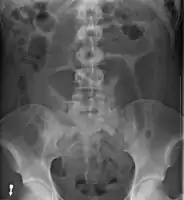

An x-ray of a person with a small bowel volvulus.

Plain X ray of a cecal volvulus